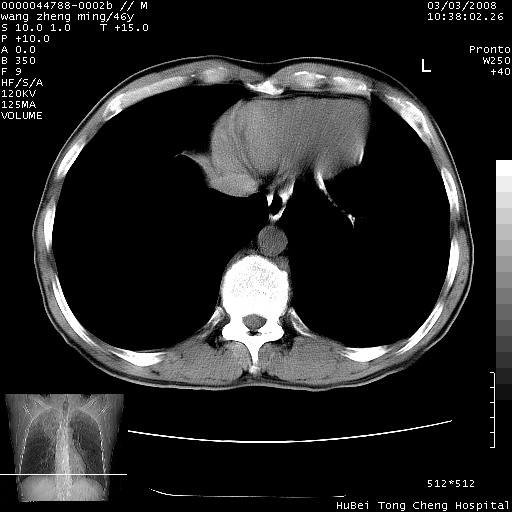

以下是引用卜一在2008-3-22 1:37:00的发言:[br]右肺实质性肿块,边缘不整,明显见毛刺征 分叶征及胸膜凹陷征,右上叶支气管明显变窄,远端散在的片状 斑片状实变影。另:左肺门较大肿块,支气管受累 变窄,远侧见阻塞性肺炎。纵隔内见肿大淋巴结。多考虑:右肺周围性肺癌伴左肺门 纵隔淋巴结转移!